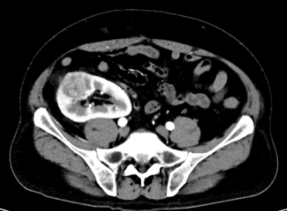

image.png CT检查提示右侧移植肾肿瘤